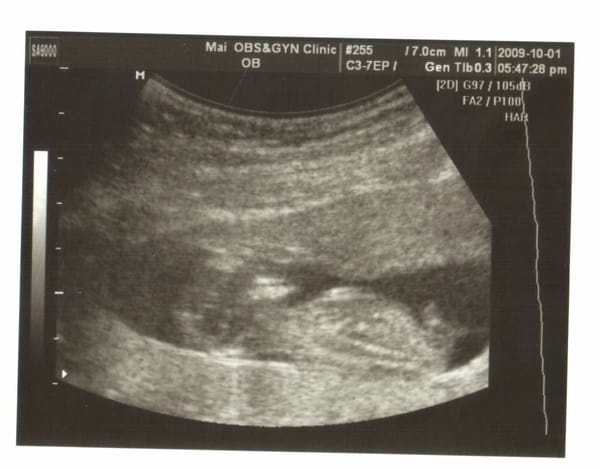

小老虎第四次產檢,驗尿ok,血壓ok,母親體重60.5KG。 小老虎上次產檢3百多公克,這次5百多公克,換句話說,這四周胖了2.7KG,結結實實胖在母體。 非常奇特,因為這幾周來我定時吃三餐沒吃消夜,這樣反而胖? 超音波照片拿到手之後,傅看著她的鼻子,說:鼻子好像比較挺喔。 小老虎還是趴著的。 有點擔心她一直趴會不會怎樣? 這次的產檢因為看不到小老虎的臉,所以醫生就用4D的給我們看 […]…